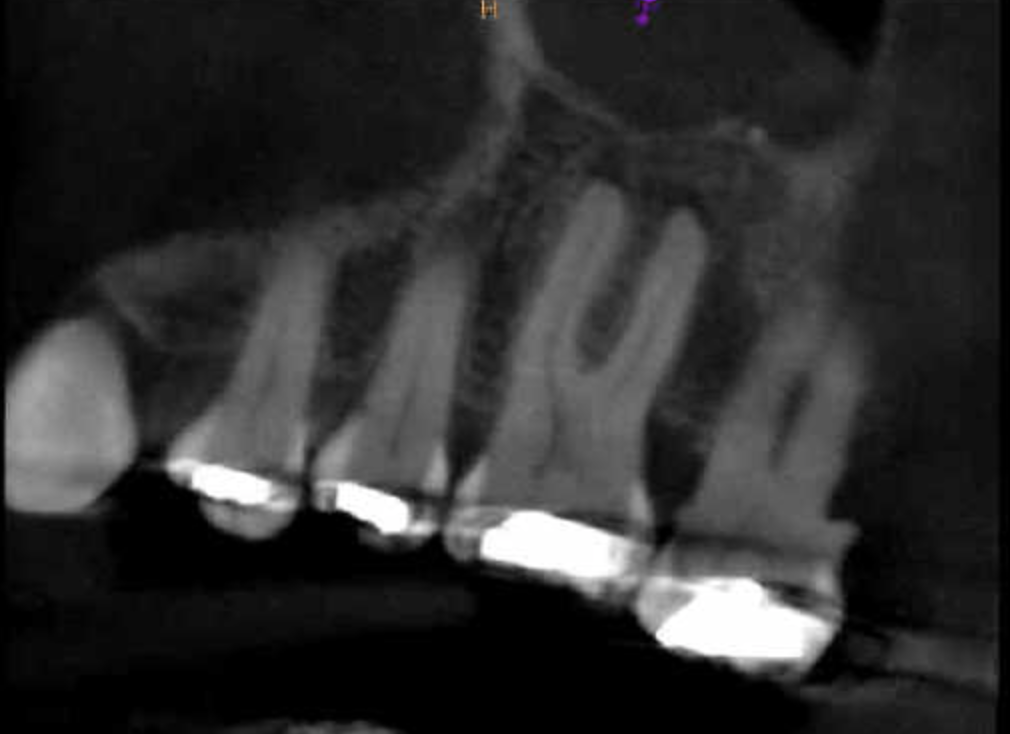

Retratamiento Molar Superior

Retratamiento Primer Molar Superior

Retratamiento, Localización 4o Conducto